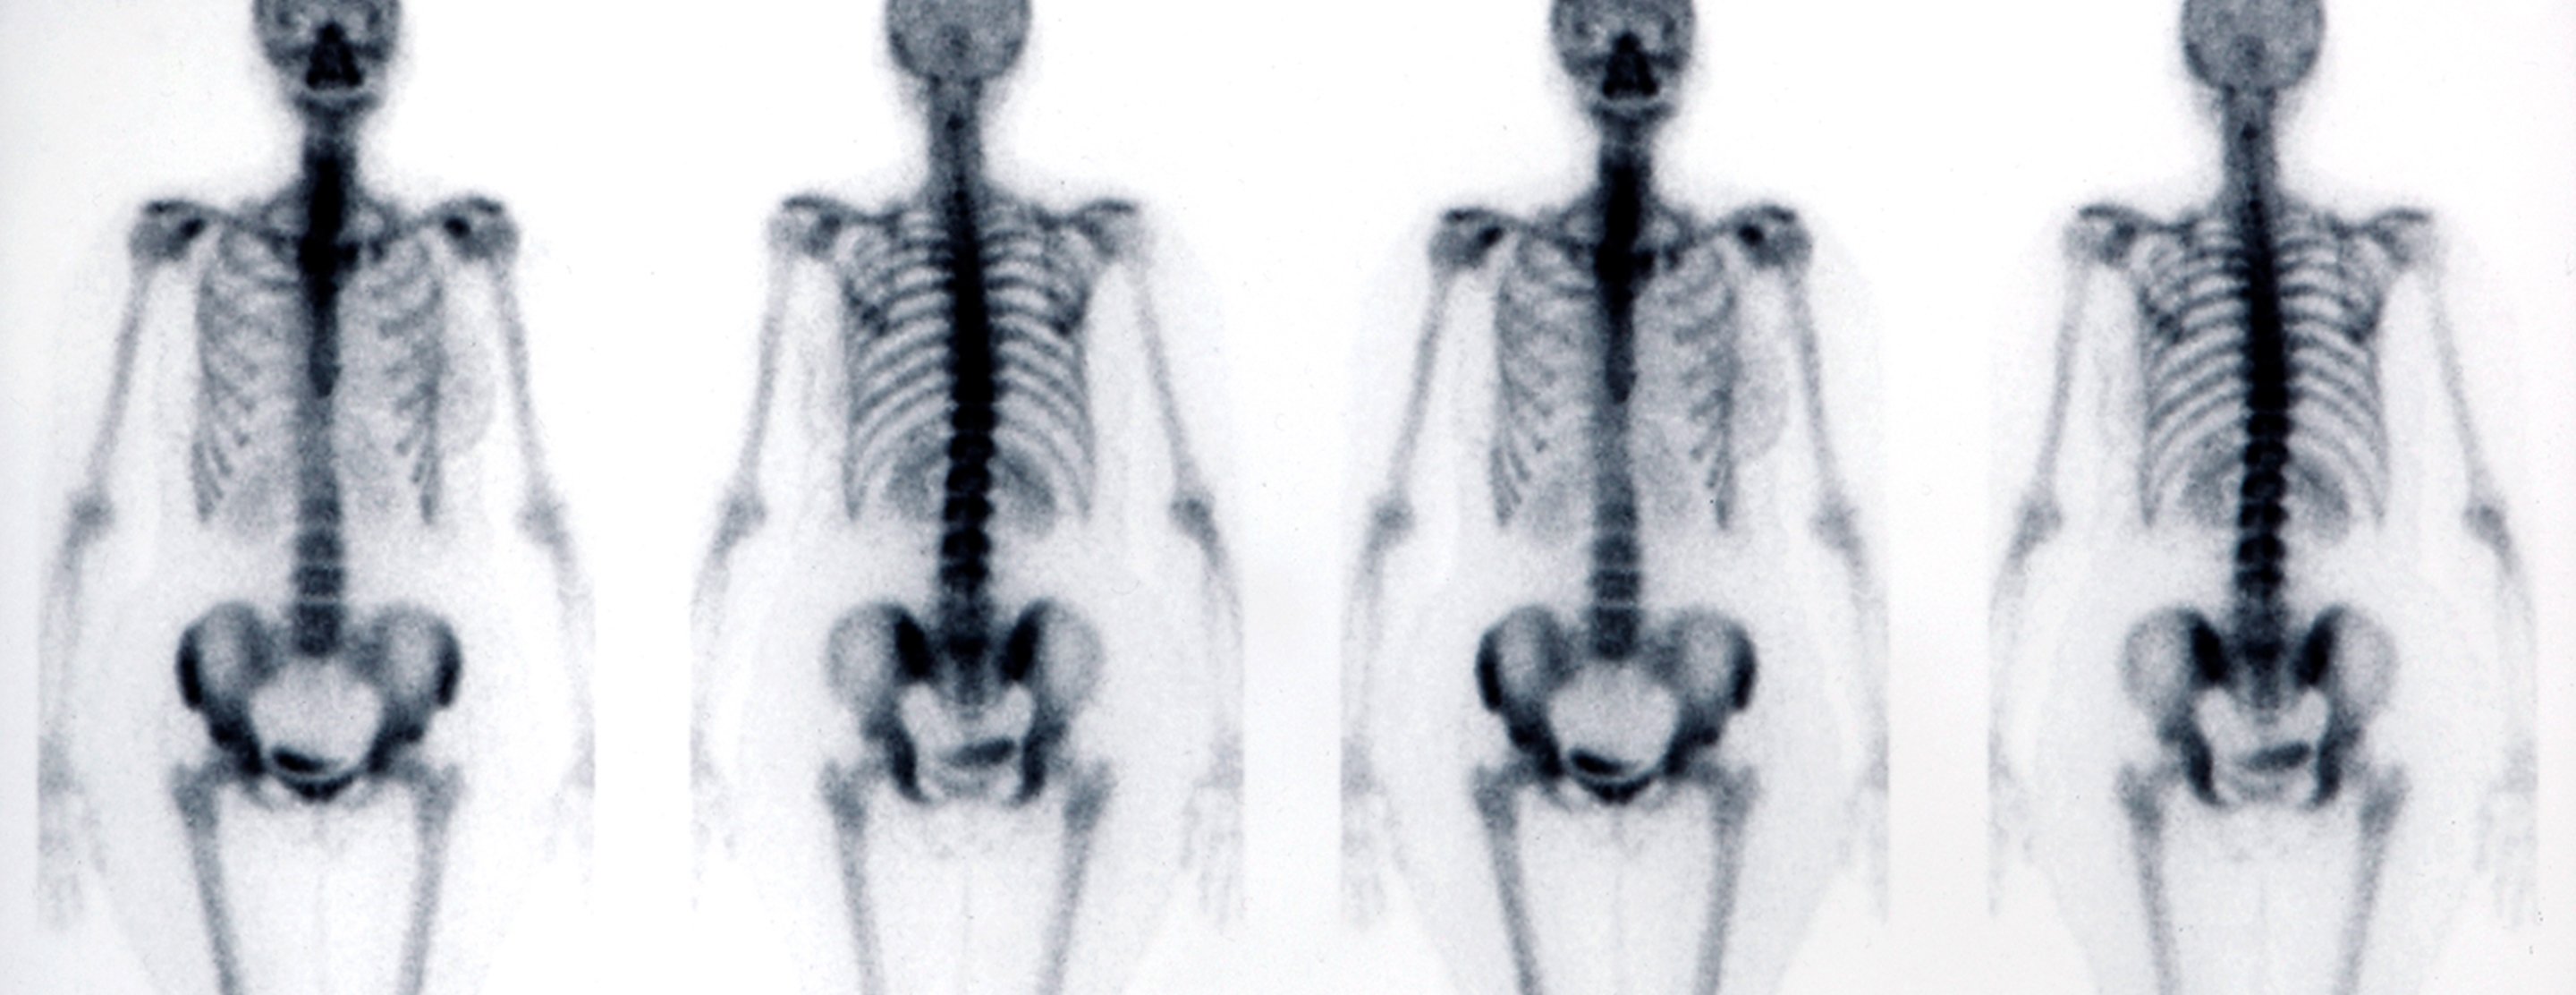

Bone scan

A bone scan is an imaging test used to diagnose bone diseases and find out how severe they are.

A bone scan involves injecting a very small amount of radioactive material (radiotracer) into a vein. This substance travels through your blood to your bones and organs. As it wears off, it gives off a bit of radiation. This radiation is detected by a camera that slowly scans your body. The camera takes pictures of how much radiotracer collects in your bones.

Test results are considered normal if the radiotracer is present evenly throughout all the bones.

An abnormal scan will show hot spots or cold spots as compared to surrounding bone. Hot spots are areas where there is an increased collection of the radioactive material. Cold spots are areas that have taken up less of the radioactive material.